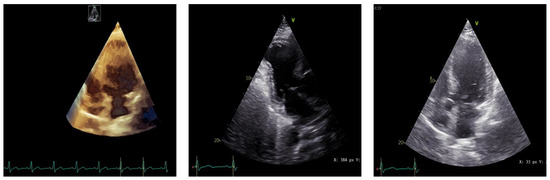

T and Small Protrusion (TAP) Technique in Bifurcations: Coronary Artery Disease in Acute Myocardial Infarction Patients after COVID-19 Pneumonia

Ischemic coronary artery disease in all its forms remains the main cause of death worldwide. Coronary artery bifurcation lesions are a challenge because of their complexity and possible complications. The goal of treating bifurcation lesions is the optimal revascularization of the main vessel without compromising the side branch. Although the study of bifurcation stenting aims to keep the side branch viable, the outcomes regarding major acute cardiovascular events and survivability are related to the optimal treatment of the main vessel. There are many trials that have tried to evaluate the best technique to use with respect to bifurcation lesions, and early studies support provisional stenting as the election treatment. More recent trials highlighted the superior outcomes of the double kissing crush technique used on unprotected distal left main bifurcation lesions. In patients with acute myocardial infarction, two-stent techniques were avoided because of the prolonged procedural time in unstable patients, with high risks of complications. We present the case of a 53-year-old woman with multiple cardiovascular risk factors (dyslipidemia, hypertension, active cancer, post-COVID-19 state) and acute antero-lateral myocardial infarction who underwent primary coronary intervention with the use of the TAP technique for stenting the bifurcation culprit coronary lesion (left anterior descendent artery and first diagonal artery). Full article

Show Figures

Graphical abstract